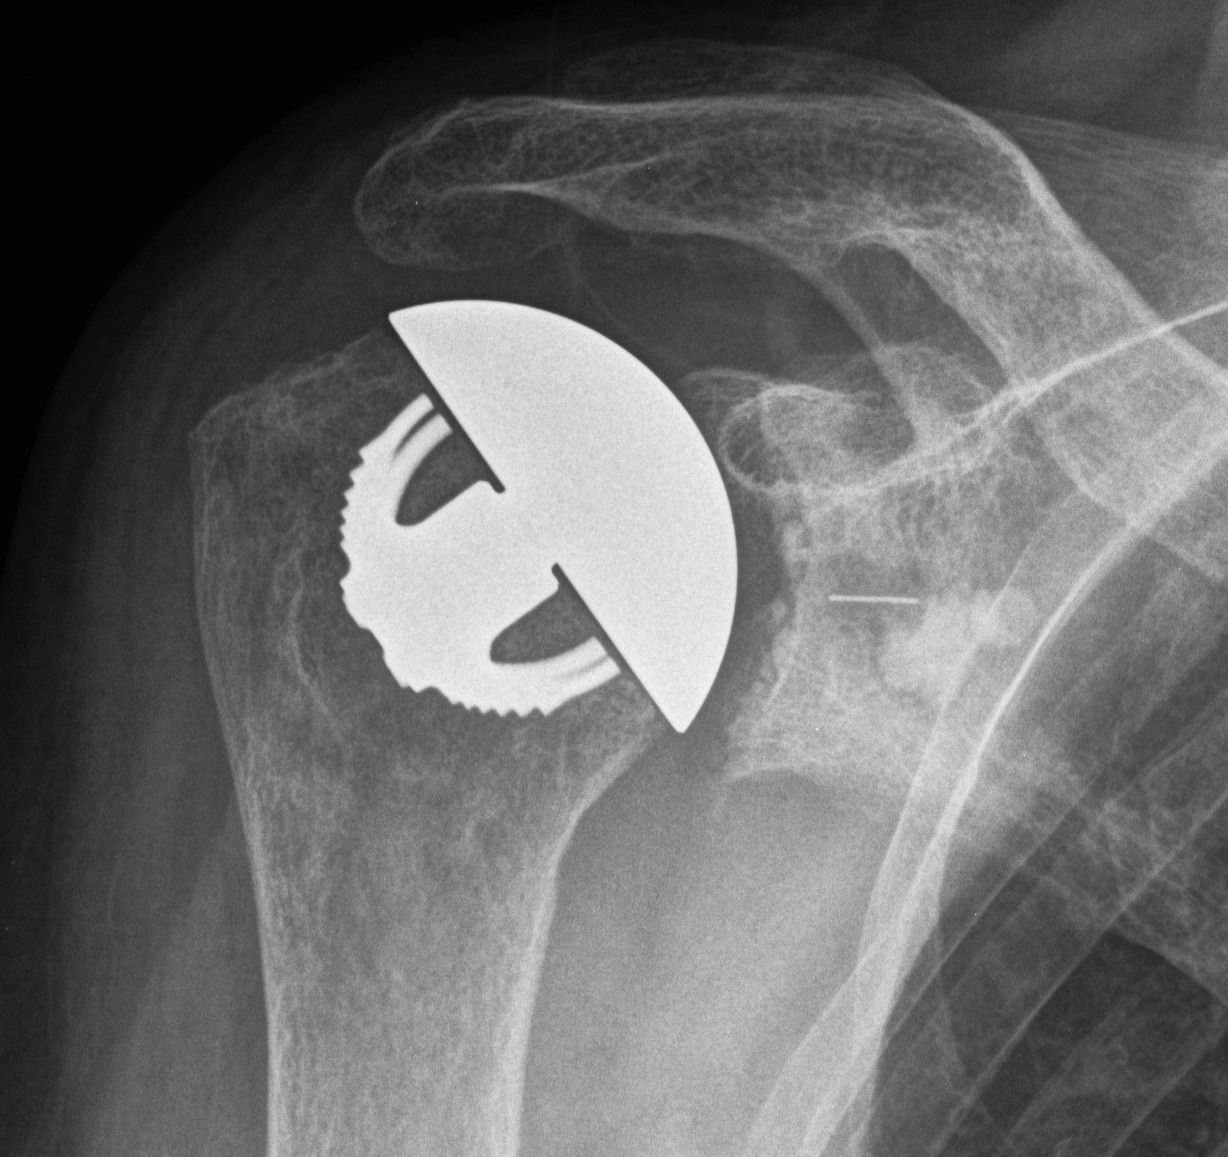

Humeral component

Modern components

Variety of thickness options of humeral head

- overstuffing of joint reduces ROM and places excessive stress on rotator cuff

Offset options

- normal head offset from neck posteriorly and medially

- placing head more anterior than normal can impinge on SSC and cause late rupture

Trial

Should be able to

A. Inferiorly sublux head 50% glenoid and return to center

B. Posteriorly sublux head 50% and return to center

C. Able to close subscapularis without impingement on head